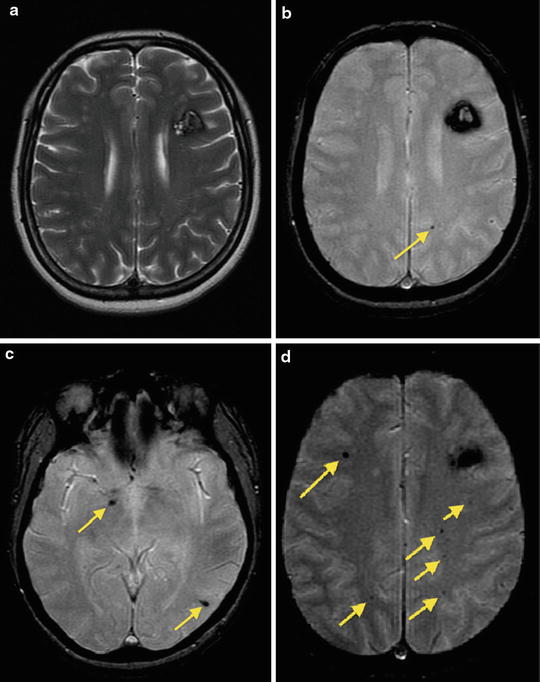

Мр картина венозной ангиомы левой гемисферы мозжечка - 96 фото